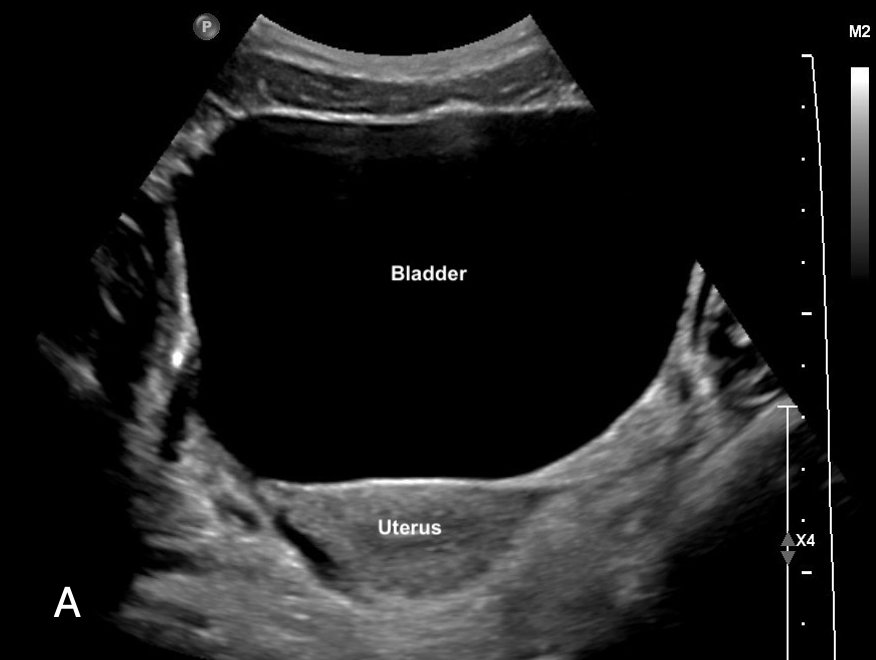

– Sits anterior to the uterus in females (figure 7a, 9a)

Figure 7ab: Sagittal bladder sonoanatomy in female (a) and male (b) children.

Figure 9ab: Transverse bladder scan sonoanatomy in female (a) and male (b) chidlren.